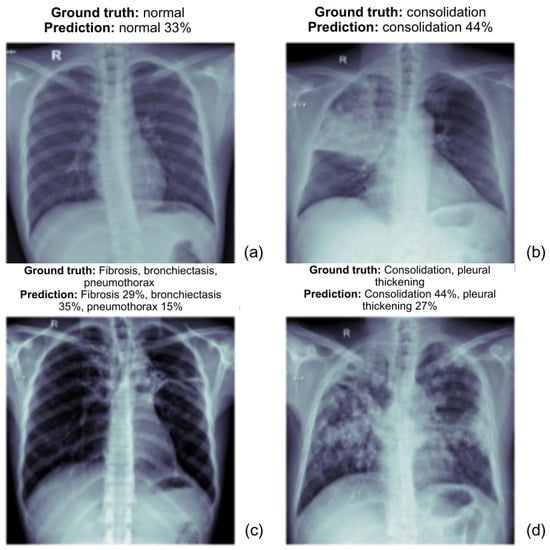

The following images as shown in the Figure 5 present the prediction outcomes from the EfficientNetV2L model. Each image includes a comparison between the actual diagnosis and the predicted diagnosis, along with the model’s confidence level for each predicted label. This analysis demonstrates the ability of both models to detect various TB-related abnormalities from chest X-ray (CXR) images.

(a)

The ground truth is normal, and the model correctly predicts it with a confidence of 33%. The prediction aligns with the actual diagnosis, though the confidence could be higher.

(b)

The ground truth is consolidation and the model predicts it with 44% confidence. The model correctly identifies the abnormality, demonstrating its potential in recognizing consolidation.

(c)

The ground truth includes fibrosis, bronchiectasis, and pneumothorax. The model predicts these conditions with fibrosis 29%, bronchiectasis 35%, and pneumothorax 15%. These predictions reflect a reasonable overlap with the ground truth.

(d)

The ground truth includes consolidation and pleural thickening. The model predicts consolidation with 44% confidence and pleural thickening with 27% confidence, which aligns well with the ground truth.